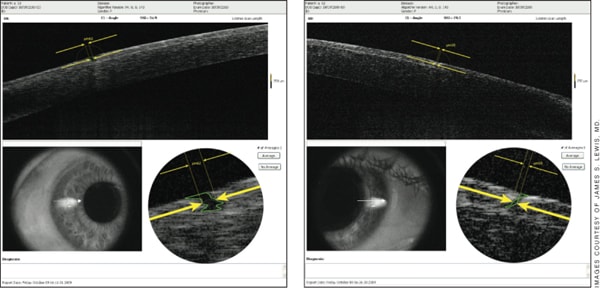

Figure 1. Left: Anterior segment OCT shows a 62-micron stromal gap between the IntraLase flap edge and the surrounding peripheral corneal bed. Right: A smaller stromal gap or “femtosecond furrow” in this immediate postop case.

When he examined the edge of the laser-made flap, he discovered something he did not expect: a break between the flap and the untouched corneal stroma peripherally. These “little gutters” he saw in the femto cases ranged from 20 to 80 microns wide. They were present in every meridian except the hinge region (Figure 1).

“That was unexpected. I was expecting the angle to be well defined, as these arguments have been made that it's so much better and so much more stable,” Dr. Lewis says. “In actuality, I found discontinuity, a total absence of stroma and possibly stromal tissue loss. A week later you don't see the gap in the OCT. What you see is an epithelial plug filling the furrow with a slightly different tissue density.”

He says he saw these gaps in every one of 30 Intralase cases performed by different surgeons. “Nothing suggestive of tissue loss was found in the SBK cases.”

In the femto cases, Dr. Lewis continues, “We do not see the well-defined edges that are theorized to make enhancement safer and epithelial ingrowth a thing of the past. In fact, what we see may be the first sign that the femtosecond laser is not a panacea.”

He suspects the possible loss of stroma may be related to the side cut the femtosecond lasers use to complete the flap. Side cuts require more energy from the laser than the lamellar portion of the cut, Dr. Lewis notes; this may be how tissue is destroyed.